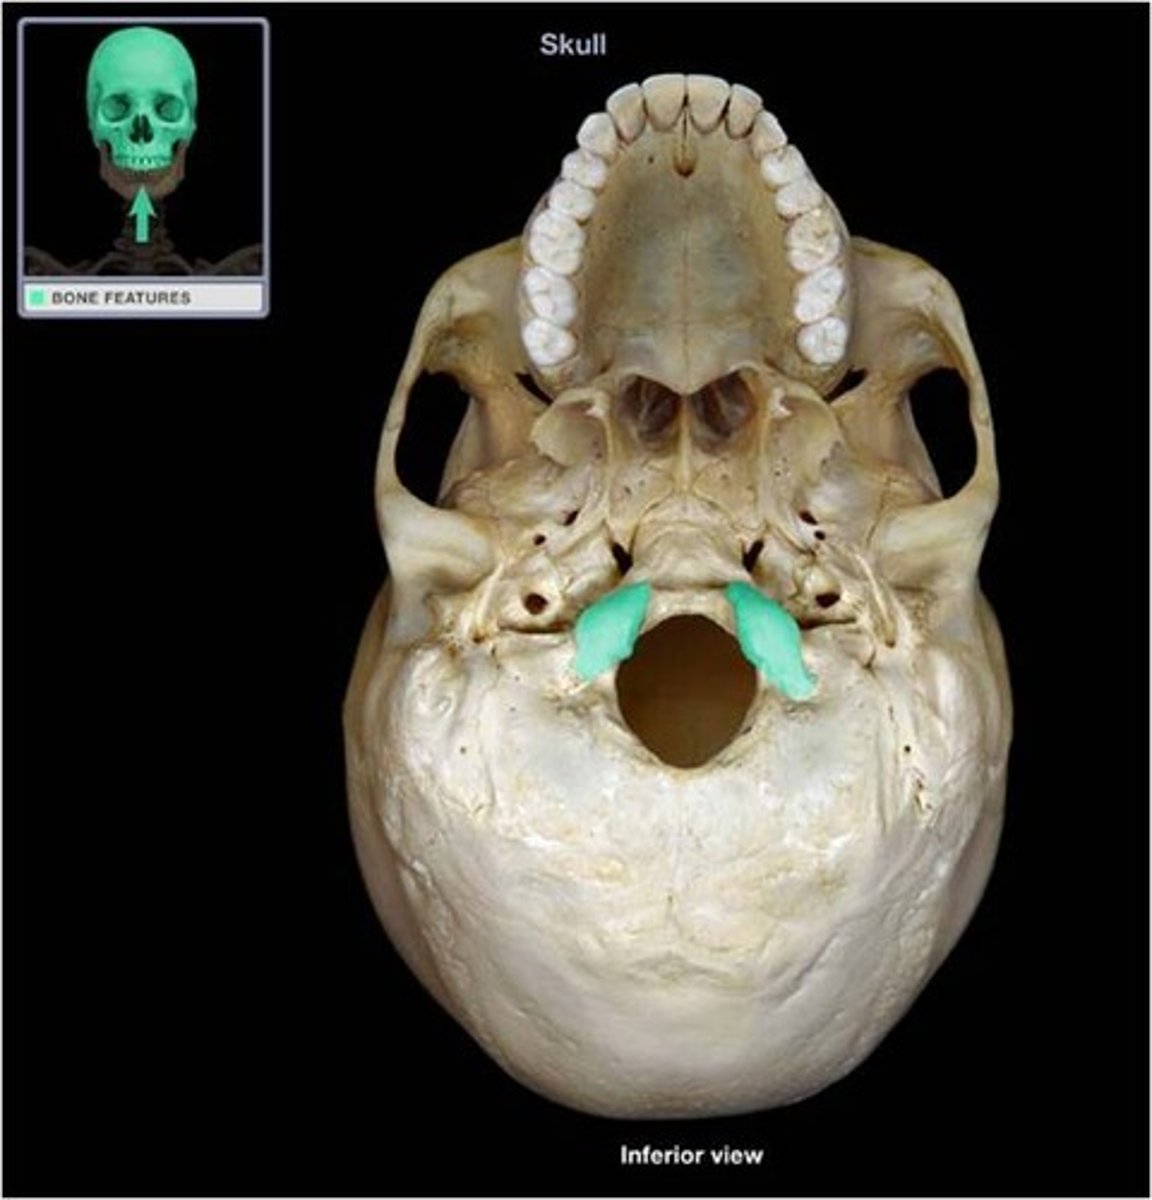

Occipital condyle